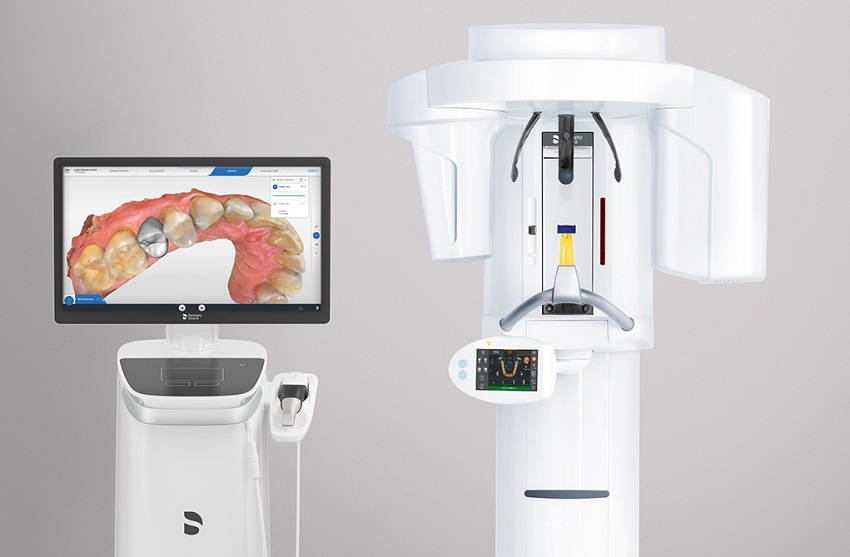

- CAD/CAM tehnologija

- 3D dijagnostika - digitalni ortopan

- Orthophos SL 3D